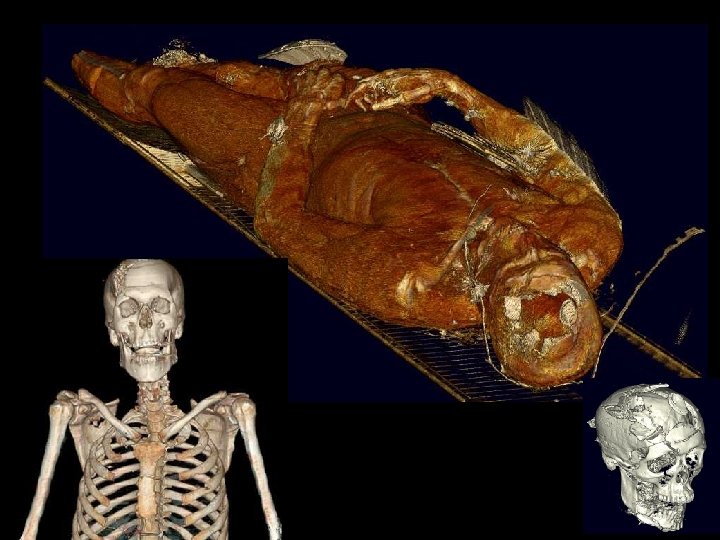

Information Representation of a Patient Medical equivalent of CAD/CAM Holomer Total body-scan for total knowledge Virtual Soldier Program Multi-modal total body scan on every trauma patient in 15 seconds Satava March, 2004

Information Representation of a Patient Medical equivalent of CAD/CAM Holomer Total body-scan for total knowledge Virtual Soldier Program Multi-modal total body scan on every trauma patient in 15 seconds Satava March, 2004